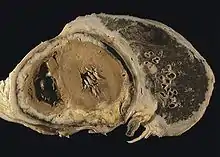

![]() | |

| CT scan showing a left sided mesothelioma with an enlarged mediastinal lymph node | |